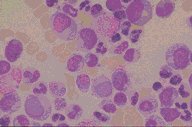

Chronic granulocytic leukemia

This bone marrow aspirate is from a patient with

chronic granulocytic leukemia in chronic phase.

There is some shift to the left, but orderly

maturation also exists. The magnification is high

dry and the stain is Wright's.